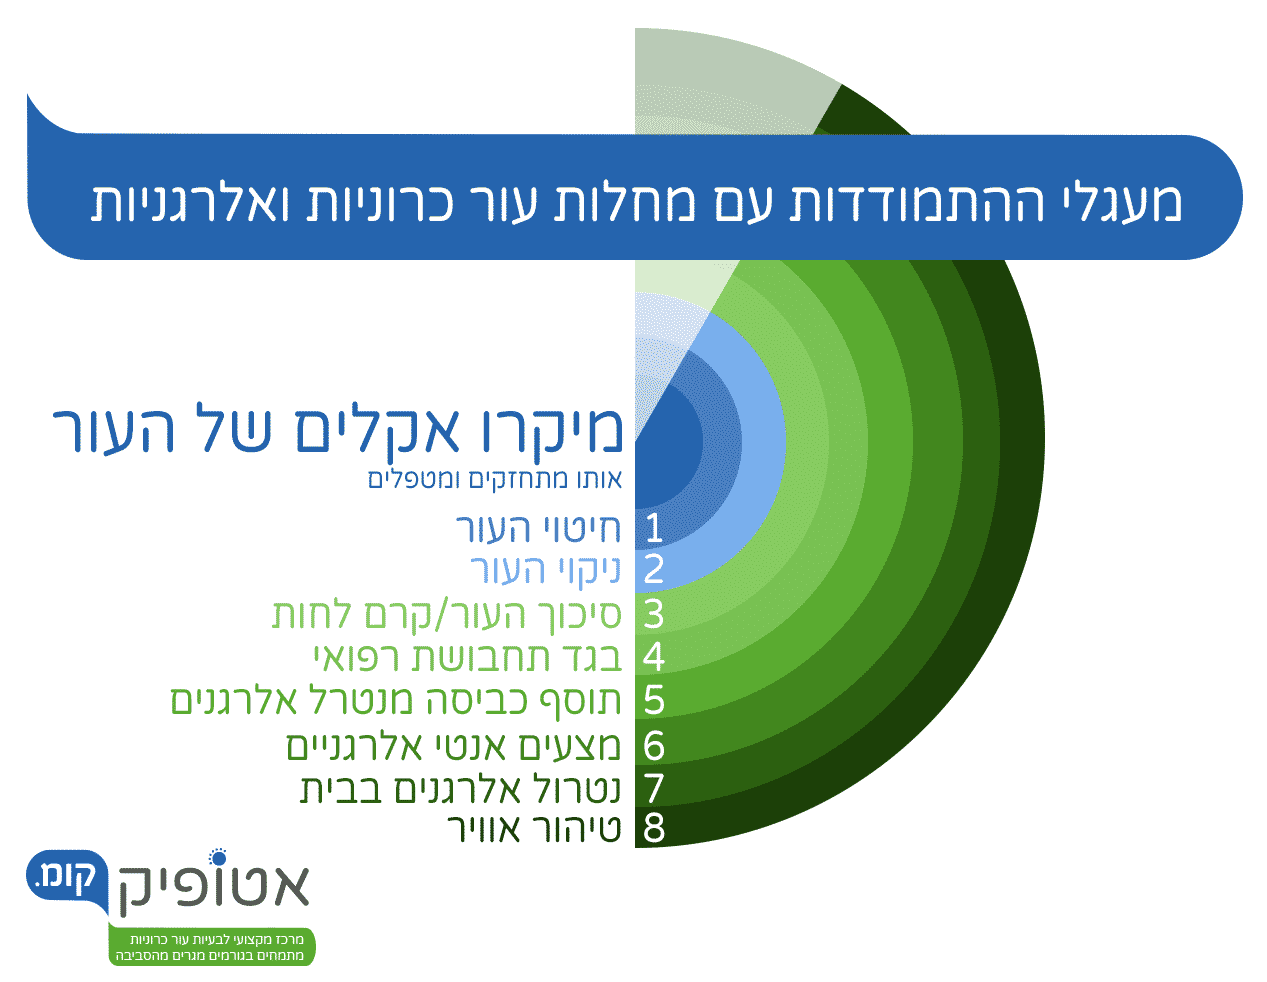

למה צריך טיפול היקפי 360°?

במהלך המסע, נצעד לאורך אבני דרך ברורות שראשיתן באבחון המחלה ועוצמתה, נבנה תוכנית טיפול אישית, נעבור דרך הטיפול בגרד ובדלקת, נצטייד בארגז כלים לבידוד גורמי המחלה, שיקום המחסום העורי וניהול המחלה, עד שנגיע אל היעד:

בשלב הראשון, לאחר קביעת האבחנה ועוצמת המחלה, נבנה עבורכם תכנית טיפול היקפית (°360) המבוססת על ״פרוטוקול עור שני״, בליווי אישי של רופאים מומחים ומטפלים עתירי ניסיון שנמצאים אתכם בזמינות גבוהה במיוחד.

כאן נתעד את המחלה, נאתר את הגורמים לה וננטרל אותם, נטפל בעור ובסביבת המחיה שלכם ונשקם את העור בעזרת טיפול תרופתי ייחודי, תכשירים ומוצרים תומכים.